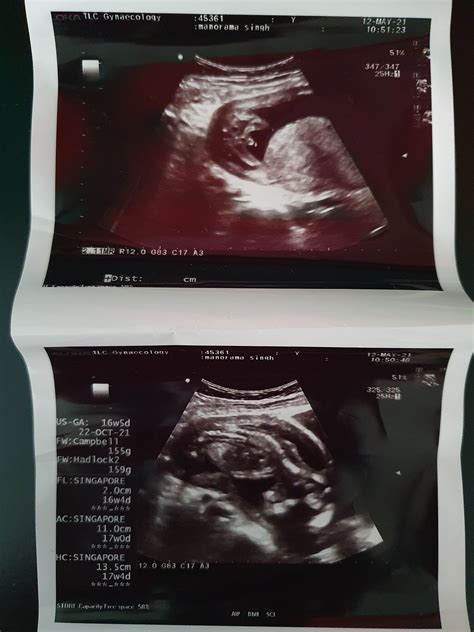

A 16 week ultrasound is a routine prenatal check-up that uses high-frequency sound waves to create images of the developing fetus. This scan is typically performed between 16 and 20 weeks of pregnancy, with 16 weeks being the most common timeframe. The primary goal of this ultrasound is to assess the baby’s growth and development, check for any potential abnormalities, and provide a clearer picture of the baby’s anatomy.

• Size and Weight: The baby is about the size of an avocado, measuring approximately 4.5 to 5.4 inches (11.4 to 13.7 centimeters) in length and weighing around 3.5 ounces (100 grams).

Understanding the Ultrasound Images

The 16 week ultrasound provides detailed images of the baby’s anatomy. Healthcare providers will look for specific features to ensure everything is developing normally. Some of the key areas of focus include: